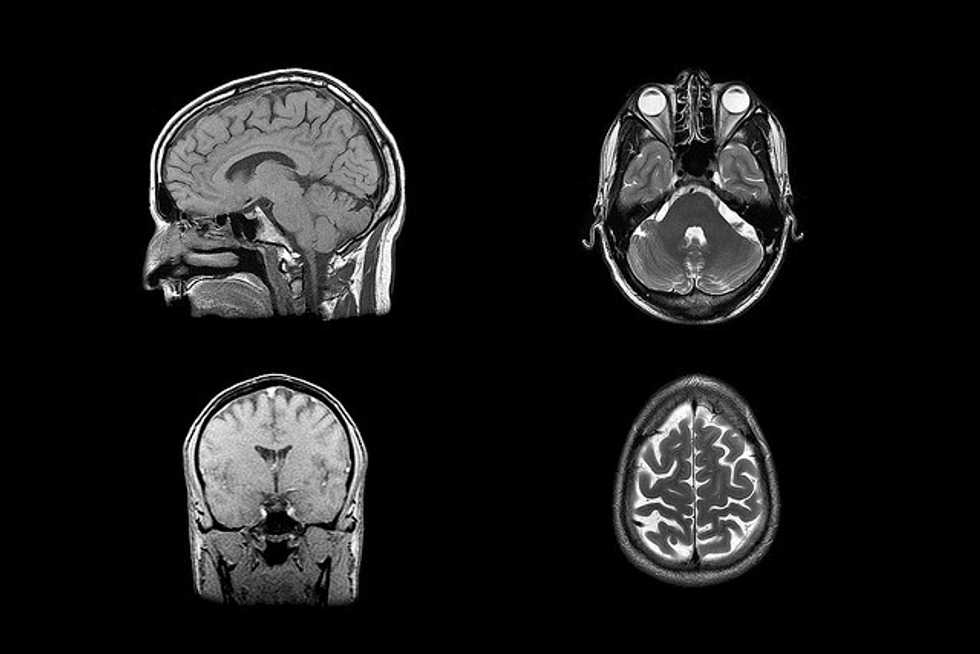

- A baby girl known as “Big Head Baby” in her Chinese village received titanium scalp implants in order to treat a rare disorder known as hydrocephalus. Hydrocephalus caused fluid retention in the brain, leading to ulcers, optic nerve damage, and a swollen cranium. Diagnosed at 6 months old, the baby, Han Han, was having trouble lifting her head and was nearly blind. The operation took 17 hours and Han Han is expected to make a full recovery.